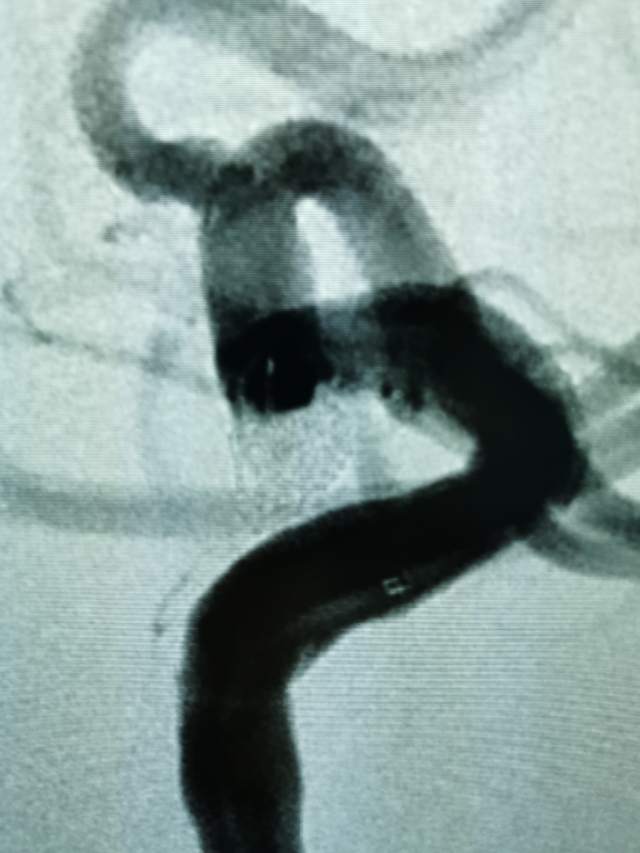

小结:患者颅内后交通动脉瘤导致的动眼神经麻痹,引起眼睑下垂、瞳孔散大、视物重影,眼球外下斜,通过远侧桡动脉入路,克服三型弓的不利解剖因素,顺利治疗了颅内动脉瘤